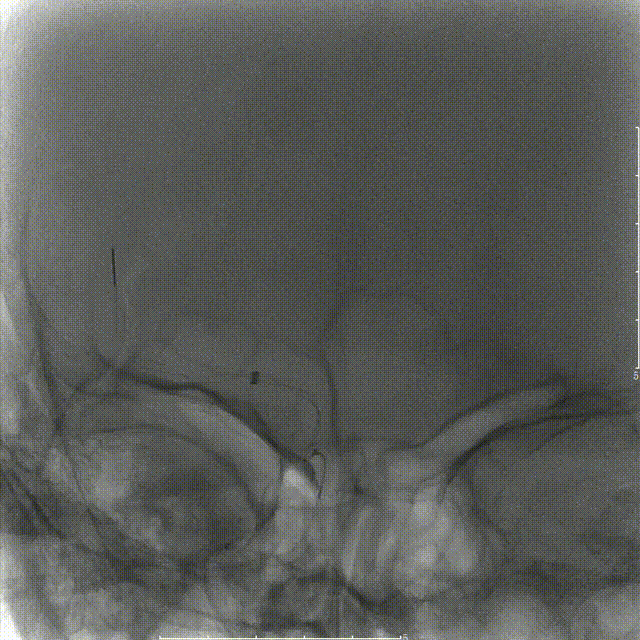

SacSpeed®球囊扩张导管 2.0*9mm球囊到位过程。

SacSpeed®球囊扩张导管 2.0*9mm球囊到位造影:血管再闭塞。

SacSpeed®球囊扩张导管缓慢扩张过程中见明显腰线。

球扩后造影:狭窄明显改善,前向血流明显好转,未见血栓征象,球囊部分回收支架,撤出。